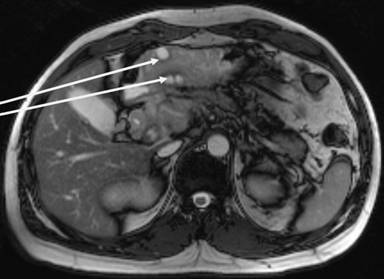

He came to the emergency room because he had felt abdominal pain in the epigastric area for two months, but the pain became constant and with increased intensity. He reported nausea and vomiting, but no modification of bowel habits. Clinical examination revealed stable hemodynamic signs but a marked tenderness with focalized guarding in the right hypochondrium and epigastric region. Laboratory analysis did not reveal anything specific, except elevated lipases at 696 U/L (reference range : 114-286 U/L). Abdominopelvic computed tomography (CT) (Figure 1) and then magnetic resonance imaging (MRI) showed kissing gastric ulcers of the antrum, with the posterior ulcus perforating the gastric wall into pancreatic parenchyma and a Balthazar C associated pancreatitis (Figures 2 and 3). Imaging also disclosed a left portal branch thrombosis and a portal biliopathy (with an amount of thin veins around the main biliary duct) (Figure 4). First, evolution was satisfactory with medical treatment (fasting, gastric protectors, and nasogastric tube). But pain returned with every attempt of food intake. Finally, an endoprosthesis in the pancreatic main duct was placed with a positive result and symptom resolution.

Figure 2. MRI showing the gastric kissing ulcers (arrows). |